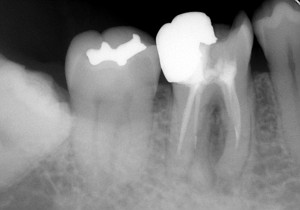

レントゲン写真で確認すると

根の先に病気がある。かぶせ物の適合も悪そう。

そして・・・

う~ん・・・(汗) どうも治療器具が折れて中に残っていそう(T_T) そのため、根の先まで治療が行えていない。